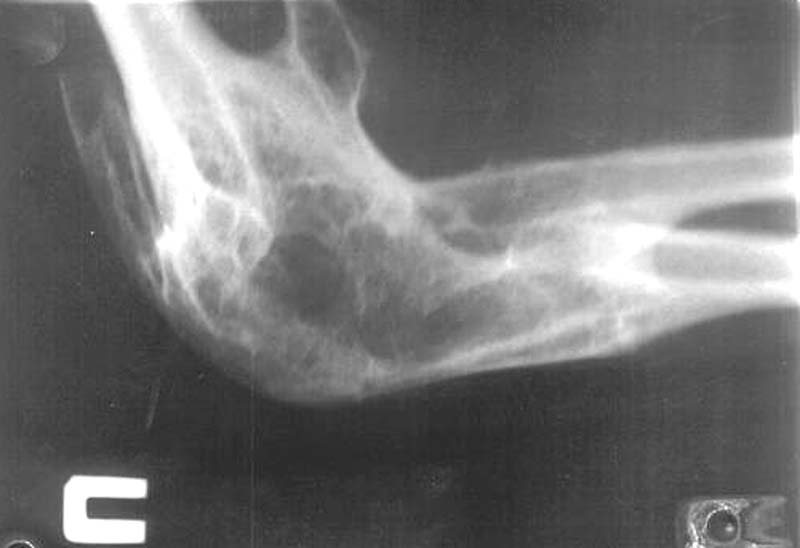

Из одного из городов нашей области к нам обратились родственники пациентки с вопросом о возможности оперативного вмешательства на локтевых суставах.К сожалени, мы ничего предложить не смогли. Ваше мнение? Каким может быть дальнейшее (оперативное, консервативное) лечение?

Женщина, 22 года, инвалид 1-й группы. В анамнезе парезы и плегии из-за разрыва аневризмы головного мозга и последующего ишемического спазма сосудов головного мозга при повторной операции. Дз: остаточные явления обширной двусторонней ишемии мозга вследствие оперативного вмешательства по поводу аневризмы ПСМА (2001 г.), нижний глубокий спастический парапарез, нейрогенные дисфункции тазовых органов, контрактуры локтевых, коленных и голеностопных суставов.КТ головного мозга: кистозно-атрофические изменения в обеих лобных долях (без динамики с 2002 г.), постинсультная киста в области колена внутренней капсулы базальных ядер справа, гипотрофические изменения в полушариях большого мозга.

Весь текст до Рг кричит: "... быть бы живу". Но если если Вы все же считаете, что больной целесообразно выполнить эндопротезирование локтевых суставов, обратитесь за консультацией к д.м.н. Жабину Георгию Ивановичу: (812)550-9530. Я его предупрежу.